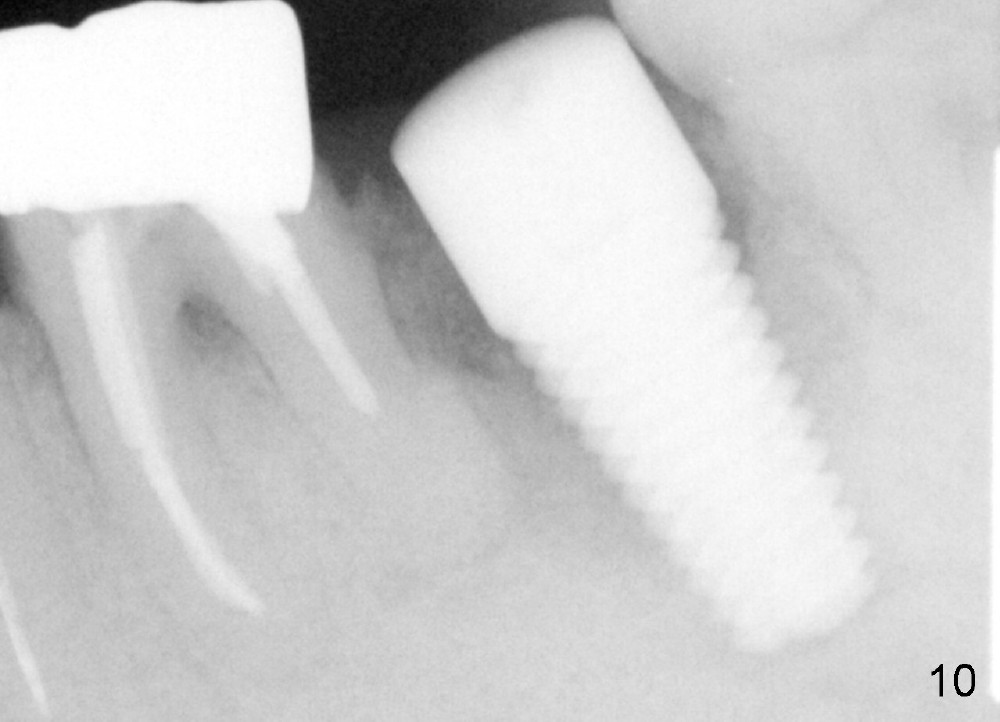

Prior to implant placement (Fig.7,9: 7x17 mm with insertion torque 40 Ncm), a mixture of autogenous bone (Fig.8 red particles) and demineralized cortical allograft (white granules) is packed against defective socket walls, particularly apically. It leaves a space in the middle of the socket for implant insertion later on. In this case, the buccal wall around the apex, corresponding to the fistula (Fig.9 >) is severely destroyed, whereas the crestal portion is more or less intact. Three months later, the implant appears yet to osteointegrate (Fig.10), while the fistula disappears (Fig.11). The large implant does not look too overengineered over the alveolus (Fig.12 (lingual view). In fact, the implant has mild mobility. How to fix it?